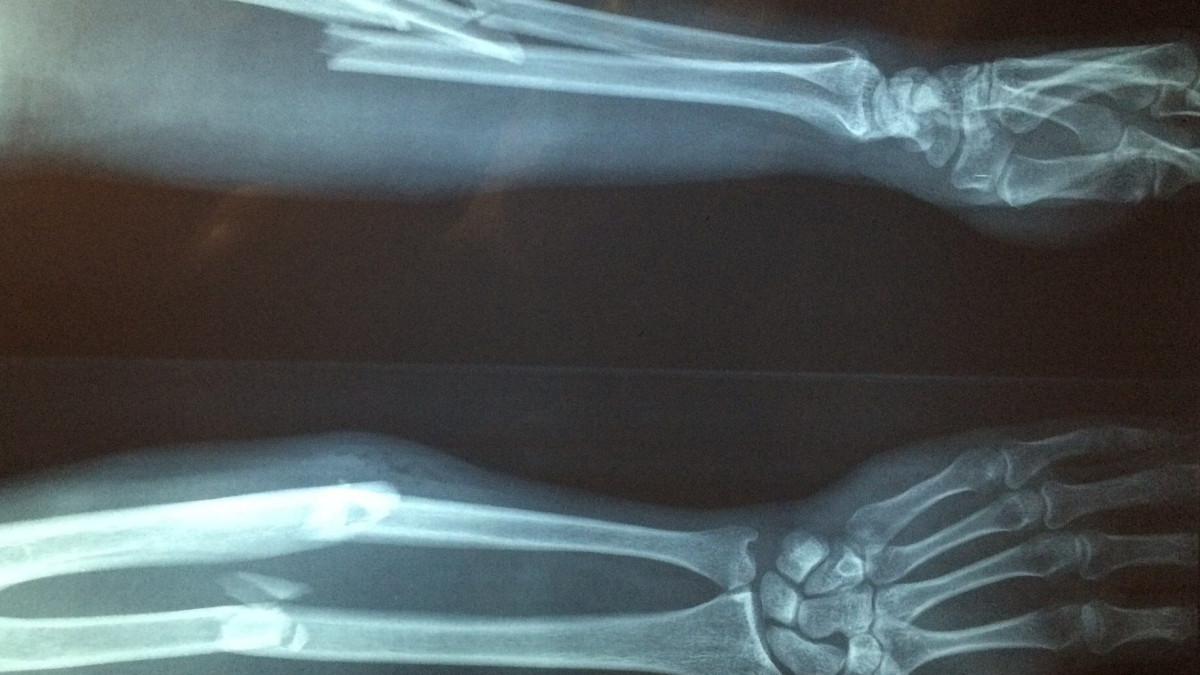

Осылайша, сүйектің бұзылу қарқыны қалпына келу процесінен басым түсіп, скелет әлсірей бастайды. Бұл сүйек сынғыштығына, деформация мен жиі болатын сынықтарға әкеледі.